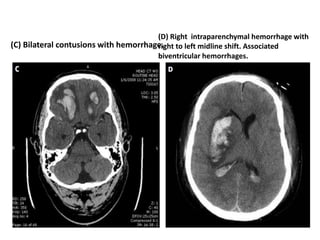

(A) Epidural hematoma. (B) Subdural hematoma

(C) Bilateral contusions with hemorrhage.

(D) Right intraparenchymal hemorrhage with

right to left midline shift. Associated

biventricular hemorrhages.